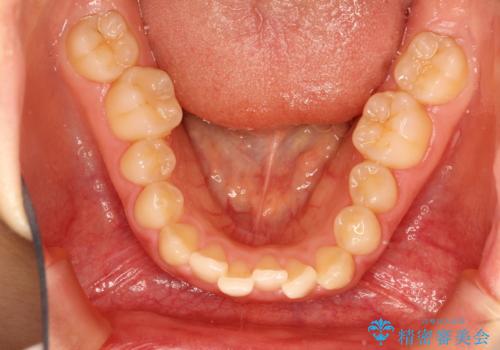

初診時の歯並びの状態としては、上下とも前歯部の中等度のがたつきがあり、その他に奥歯の噛み合わせのズレや、口元の突出感も認められました。

抜歯矯正の可能性もご提案しましたが、ご本人の強い希望もあり、抜歯なし/インビザラインによるマウスピース矯正にて治療を行いました。